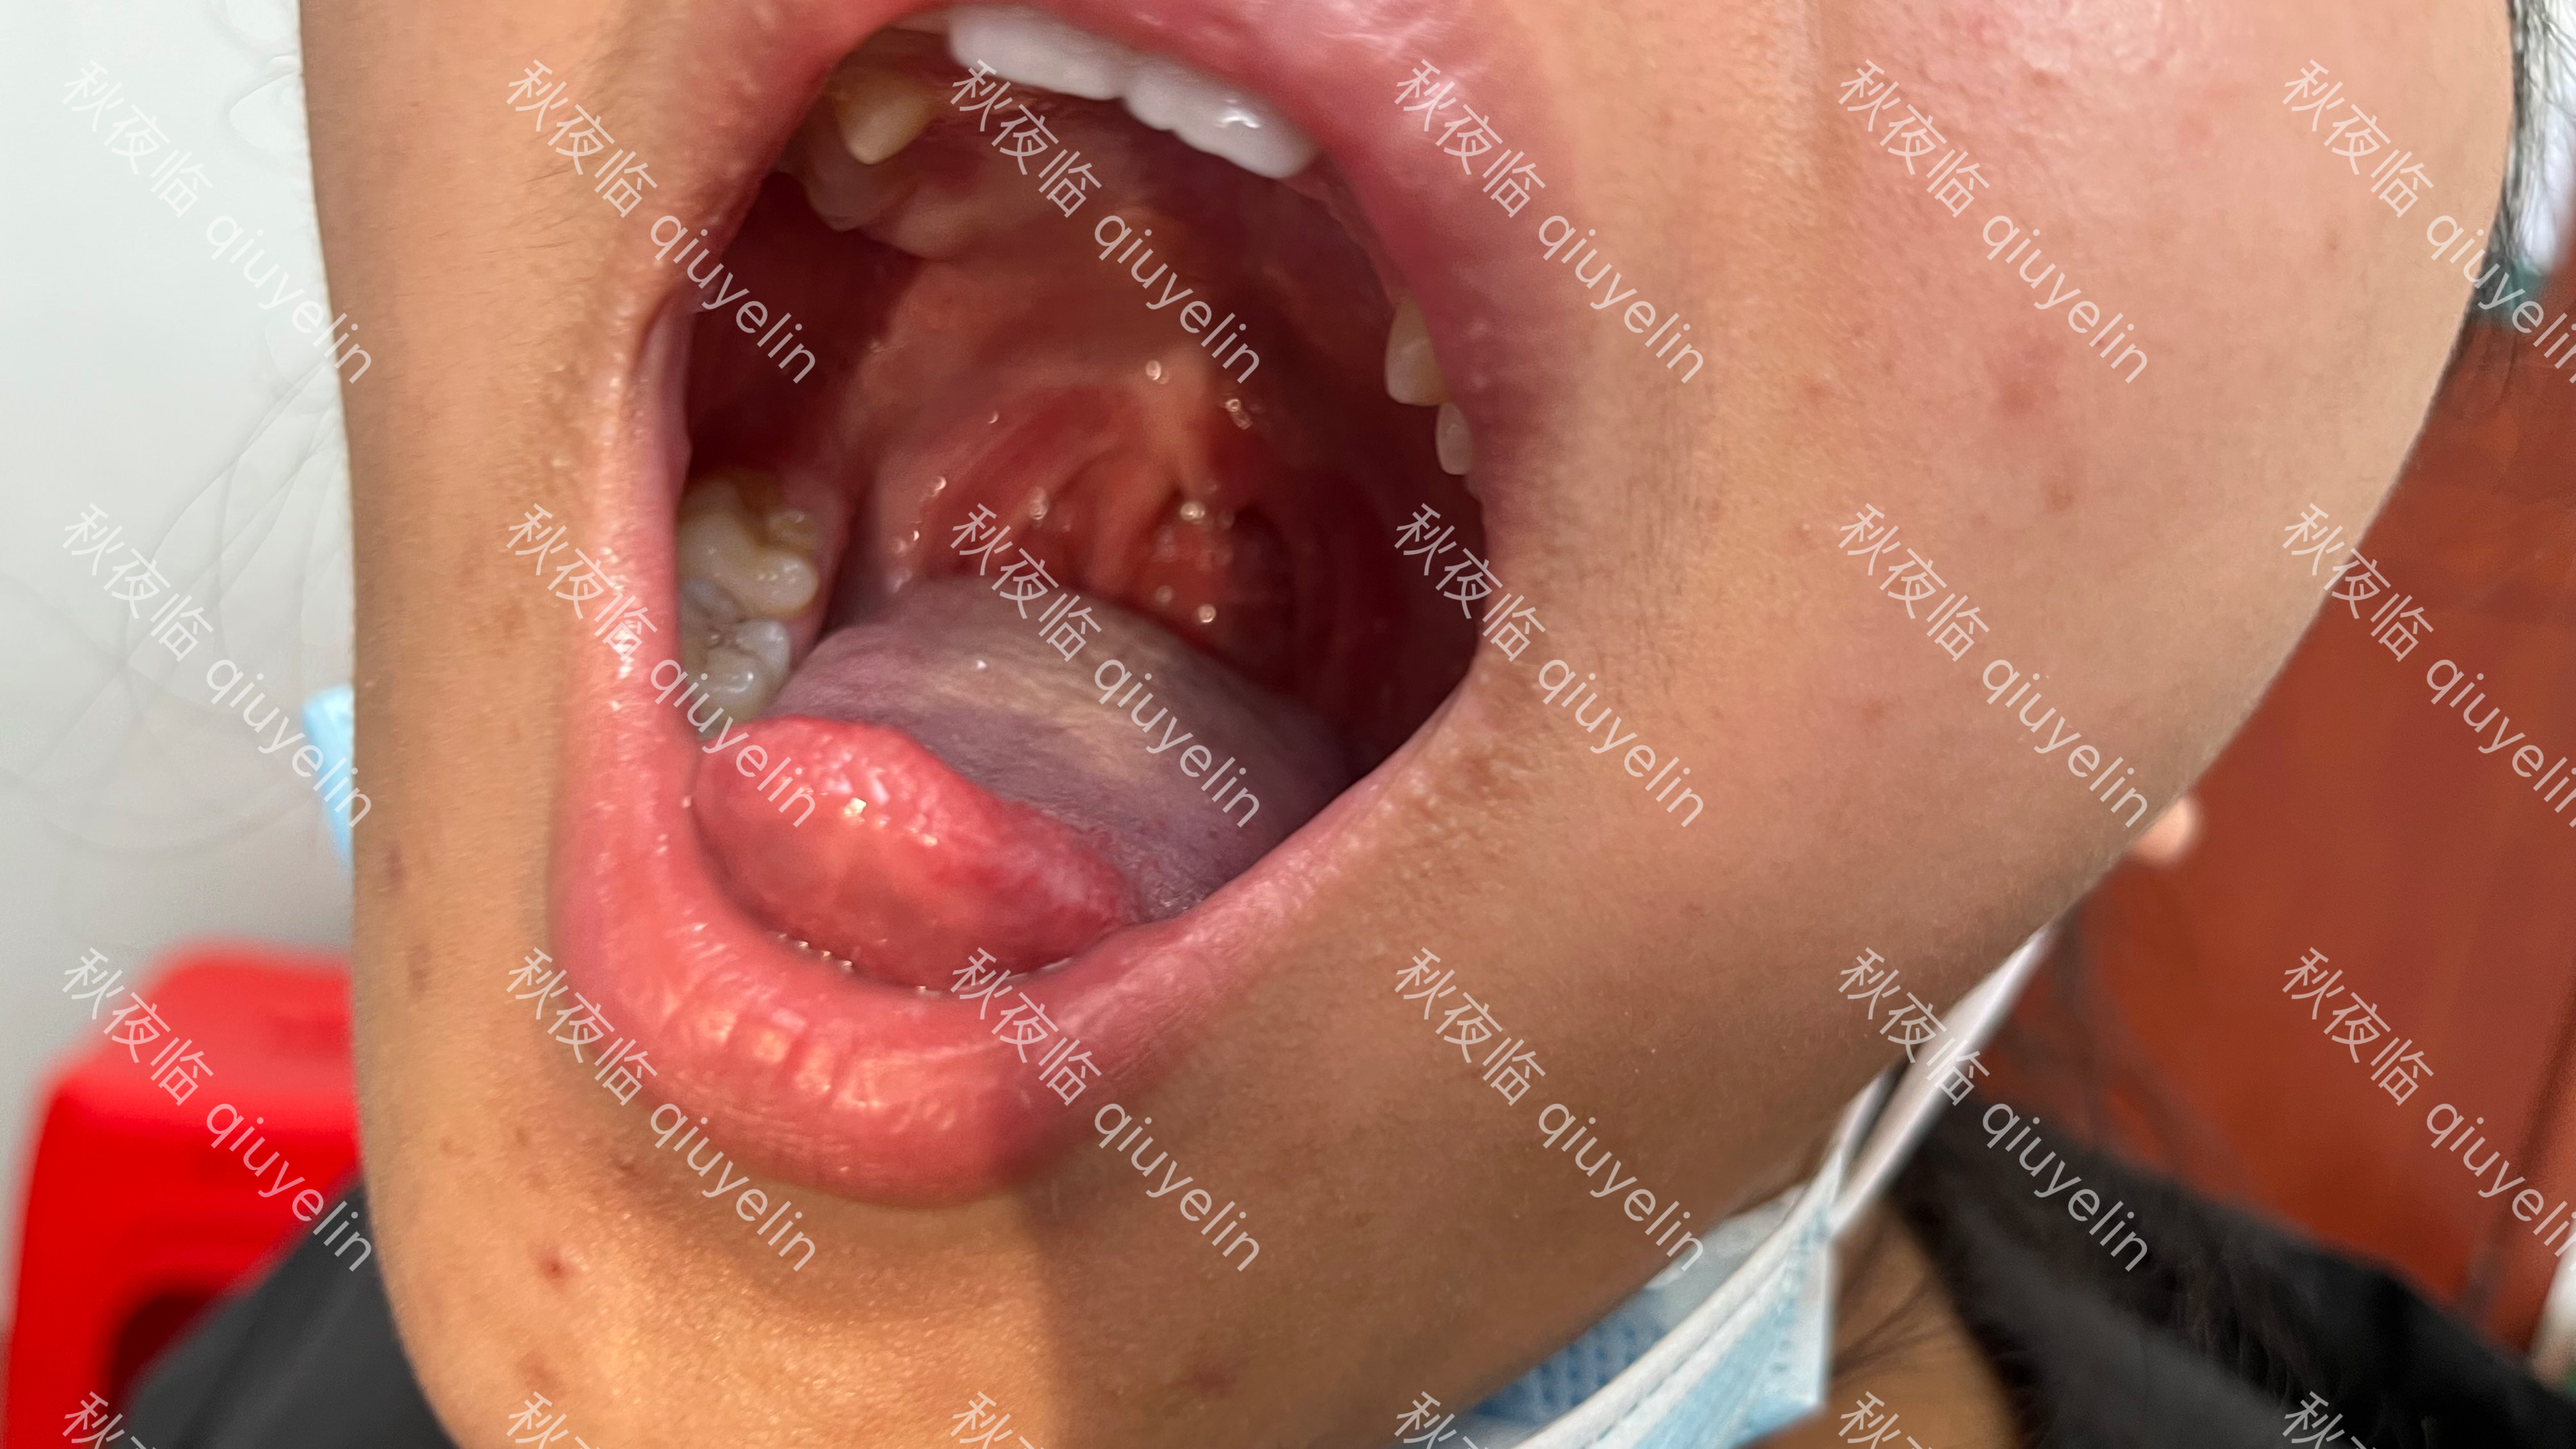

手足口病(HFMD)也称“手口足综合征”,是由肠道病毒感染引起的急性发热出疹性传染病,主要表现为手、足、口腔等部位的皮疹及疱疹以及全身发热。某些重症病例中可并发脑膜炎、脑炎、急性弛缓性麻痹、呼吸道感染和心肌炎等,少数极度重症患儿病情进展快、死亡风险大。传染方式多样,包括直接接触感染者的鼻咽分泌物、唾液等,或接触被病毒污染的物品。

手足口病的临床表现具有复杂性和多样性。大多数患者症状轻微,可伴有或不伴有发热,以手、足、口腔、臀部等部位的散在皮疹或疱疹为主要特征;少数患者可伴有多种并发症;个别重症患儿病情进展快,可发生死亡。